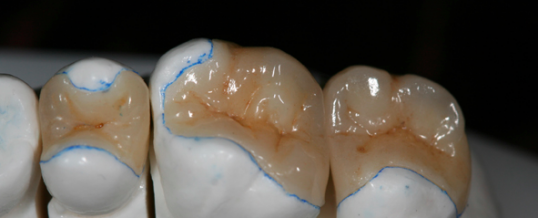

- INLAY: Incrustación que no abarca ninguna cúspide dental

- ONLAY: Incrustación que abarca al menos una cúspide sin cubrirlas todas.

- OVERLAY: Cubrimiento cuspídeo completo.